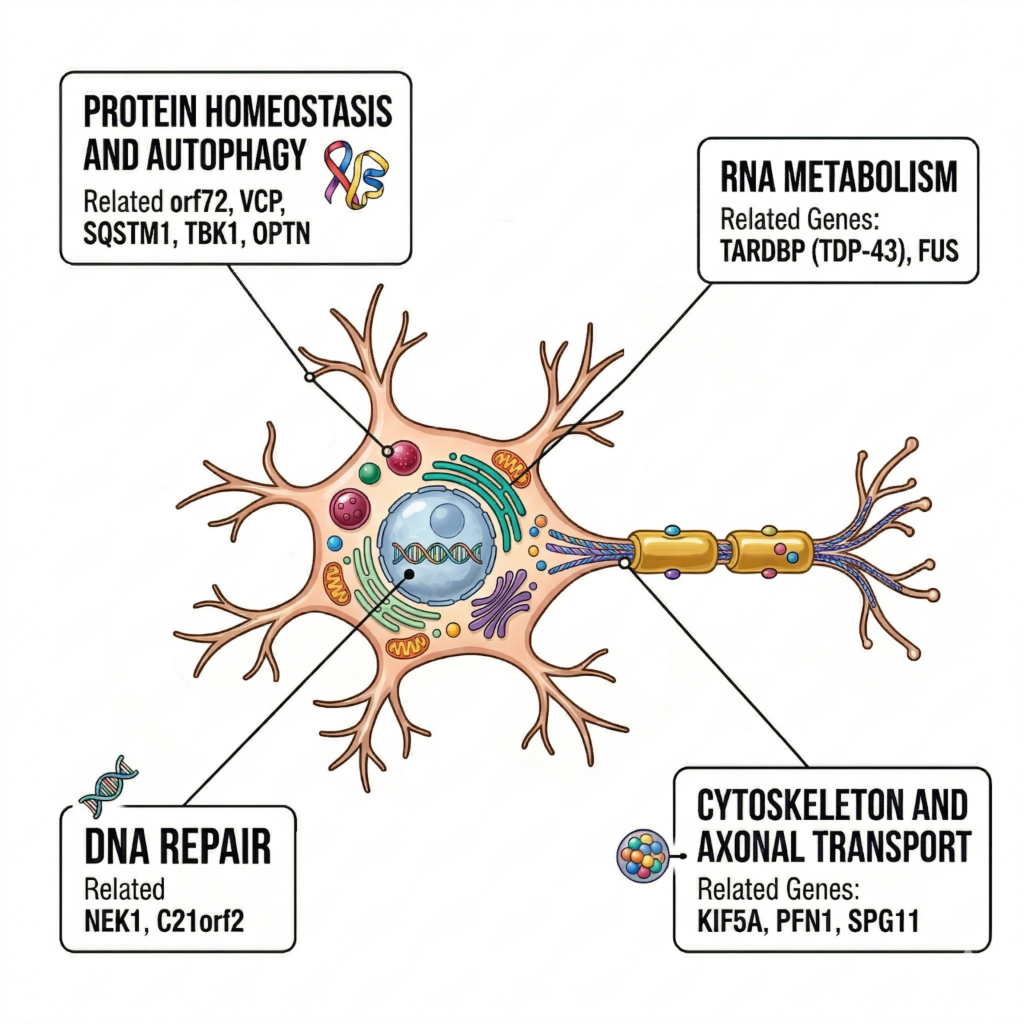

이 외에도 VCP, TBK1, OPTN, SQSTM1, CHCHD10, KIF5A, NEK1 등 다양한 유전자들이 보고되어 있으며 이들은 아래와 같은 서로 다른 세포 기능에 관여합니다.

이들은 각각

- 단백질 분해 / autophagy

- RNA metabolism

- DNA repair

- 세포 골격 유지/축삭 수송

8. 유전자들을 보면, ALS의 본질이 보인다

ALS 관련 유전자들을 보면 하나로 겹치는 공통된 특징이 없습니다.

왜냐하면 ALS는 단일 pathway 질환이 아니기 때문입니다.

주요 축:

- 단백질 항상성 / autophagy (C9orf72, VCP, SQSTM1, TBK1, OPTN)

- RNA metabolism (TARDBP (TDP-43), FUS)

- DNA repair (NEK1, C21orf2)

- cytoskeleton & axonal transport (KIF5A, PFN1, SPG11)

이걸 한 문장으로 정리하면:

👉 ALS는 “하나의 문제”가 아니라

👉 뉴런 유지 시스템 전체의 붕괴입니다